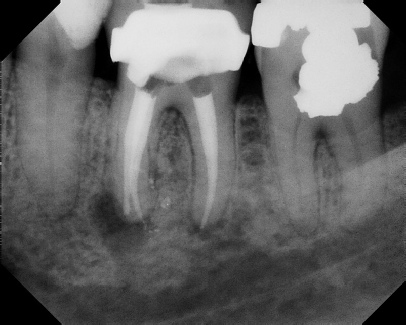

COMPLICATED ANATOMY LARGE LESIONS CALCIFIED CANALS PERFORATION / RESORPTION SEPARATED INSTRUMENTS SURGICAL CASES RETREATMENT / pOST REMOVAL OPEN APICES ACCESS THRU CROWNS Root Canal Case Portfolio

Pre-op Post-op 1 Post-op 2